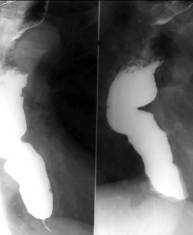

Achalazia este o stare de permanenta contractie a cardiei care produce dilatarea esofagului supraiacent. Stagnarea alimentelor la nivelul esofagului determina un proces inflamator al mucoasei cu lichid de staza. Aceasta poate produce o aspirare traheala a continutului esofagian, ceea ce induce modificari inflamatorii cronice de tip alveolar sau interstitial.

Imagistic la examenul cu bariu cardia apare mult īngustata cu contururi bine delimitate, netede, cu pliuri paralele, centreaza segmentul supraiacent. Esofagul toracic este dilatat īn grade variabile uneori foarte mult si depasind contururile mediastinului.

Concomitent esofagul se alungeste si se cudeaza. Undele peristaltice initial sunt frecvente, profunde, dar ineficiente. Evacuarea este lenta īn cantitate mica.